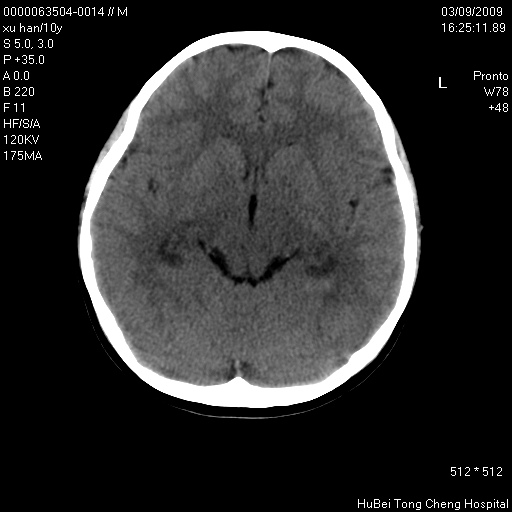

以下是引用道哥在2009-3-9 18:40:00的发言:[br]未见明显异常,必要时mr(dwi)成像。

以下是引用余辉在2009-3-10 11:01:00的发言:[br]考虑双侧海马急性缺氧性损伤